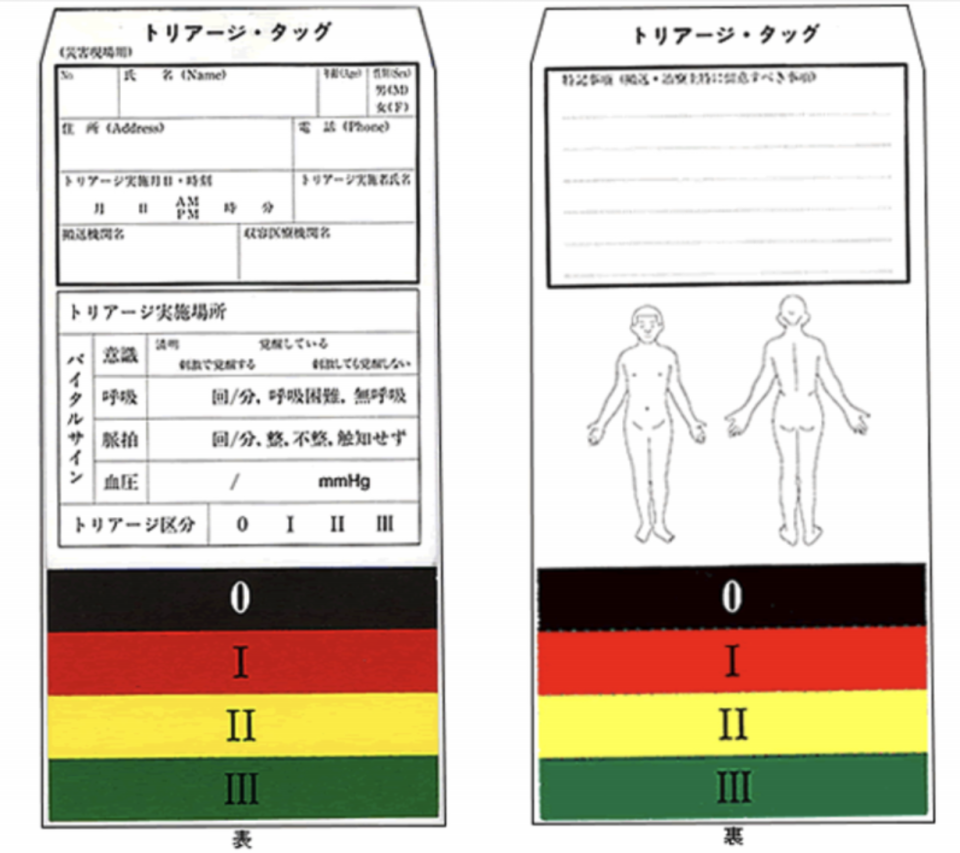

外傷の評価として基本的には「ABCD」を評価

A(Airway):気道

B(Breathing):呼吸

C(Circulation):循環

D(Dysfunction of central nervous system):中枢神経機能異常

MARCHという考え方の評価

M(Massive hemorrhage):大量出血

A(Airway):気道

R(Respiratory):呼吸

C(Circulation):循環

H(Hypothermia):低体温、Head injury(頭部外傷)の評価